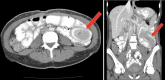

Intussusception is defined as the invagination of one segment of the bowel into an immediately adjacent segment of the bowel. Idiopathic ileocolic intussusception is the most common form in children and is typically managed with nonoperative reduction via pneumatic and/or hydrostatic enemas. In the adult population, intussusception is uncommon and occurs more often in the small intestine than in the colon. It is associated with lead point pathology in most symptomatic cases presenting as bowel obstruction. When lead point pathology is present in adult small bowel intussusception, it is usually benign, though when malignant it is most frequently due to diffuse metastatic disease, for example, melanoma. In contrast, adult ileocolic and colonic intussusception lead point pathology is most frequently primary adenocarcinoma when malignant. The diagnosis is typically made intraoperatively or by cross-sectional imaging. With increasingly frequent CT/MRI of the adult abdomen in the current era, transient and/or asymptomatic intussusceptions are increasingly found and may often be appropriately observed without intervention. When intervention in the adult population is warranted, usually oncologic bowel resection is performed due to the association with lead point pathology.